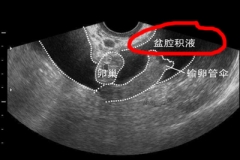

超声介入配合中药灌肠治疗盆腔积液

盆腔积液的发生多见于盆腔炎以及附件炎、子宫内膜异位症等妇科疾病后,有生理性和病理性之分,对于生理性的积液无须理会,病理性的积液要及时治疗。目前针对盆腔积液来说,...